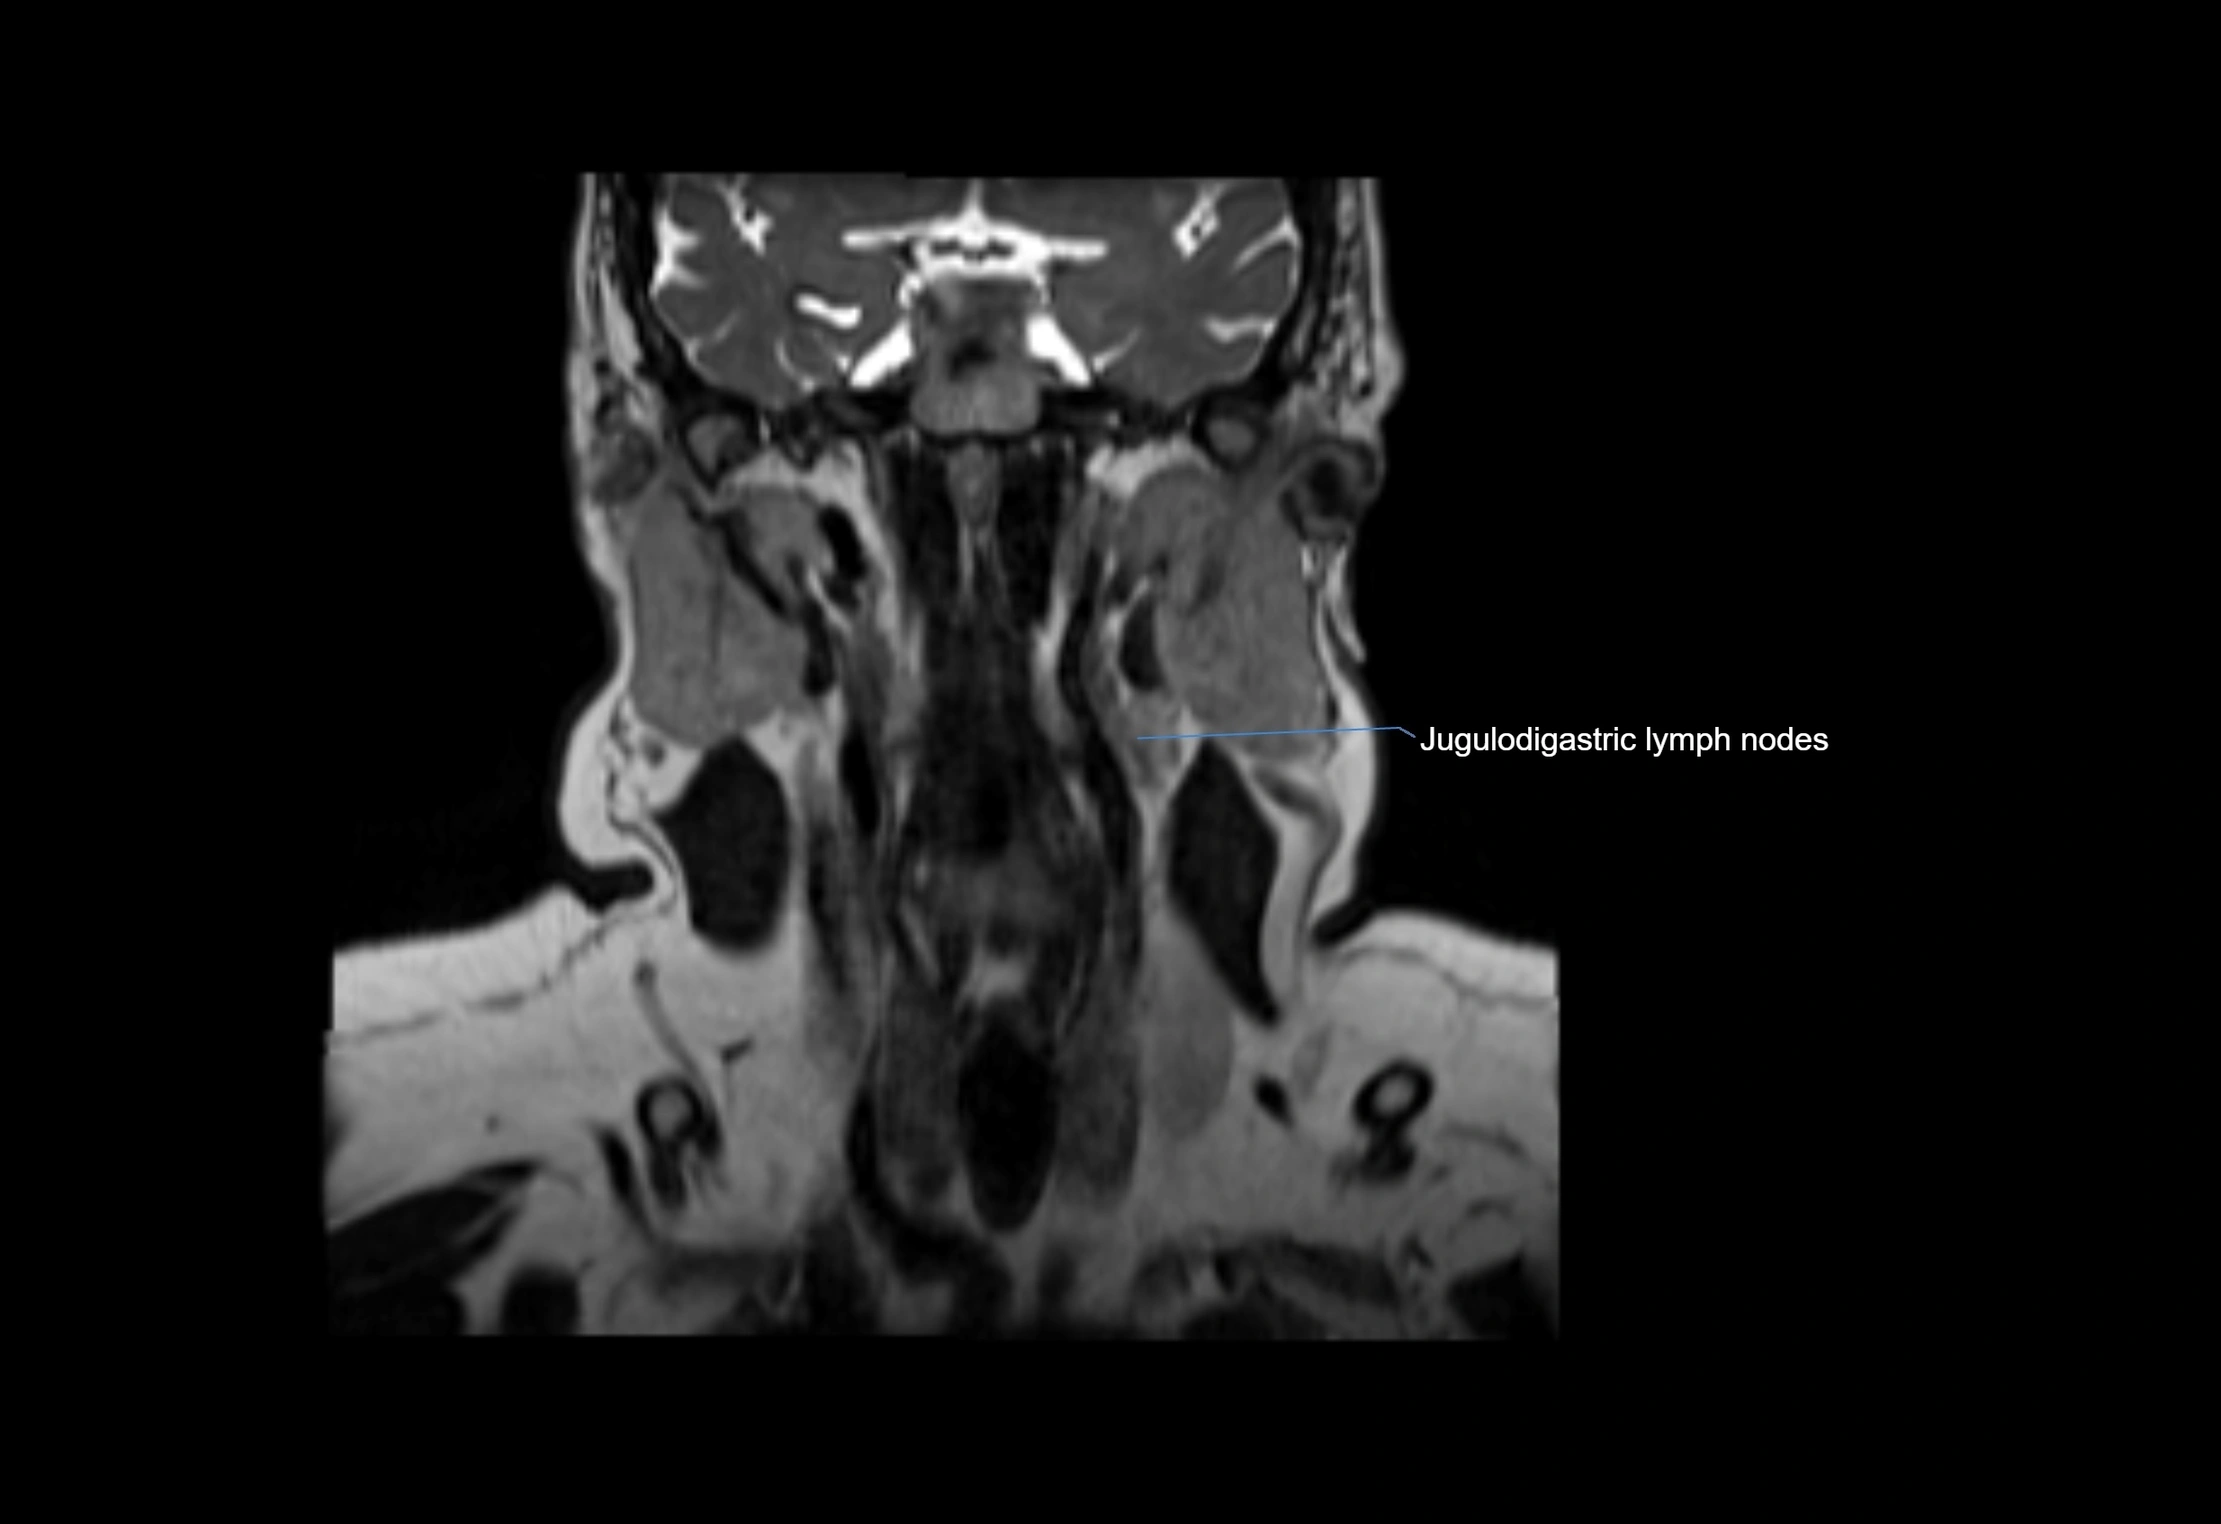

Accessory lymph nodes are small, secondary lymph nodes located along the main facial and cervical lymphatic chains, often adjacent to primary lymph nodes, such as preauricular, submandibular, or occipital nodes. They are typically less than 5 mm in diameter, embedded within subcutaneous fat or connective tissue, and may be variable in number and location. These nodes provide additional filtration and immune surveillance for lymph collected from the face, scalp, and neck regions. Accessory lymph nodes are usually non-palpable in healthy individuals but may enlarge in response to infection, inflammation, or metastasis, making them clinically significant.

Location

• Found along primary lymph node chains, including preauricular, submandibular, parotid, and occipital regions

MRI Appearance

T2-weighted images:

• Nodes show intermediate signal, with surrounding fat bright

• Useful for detecting edema, inflammation, or infiltration

• Fatty hilum may appear slightly hyperintense relative to cortex